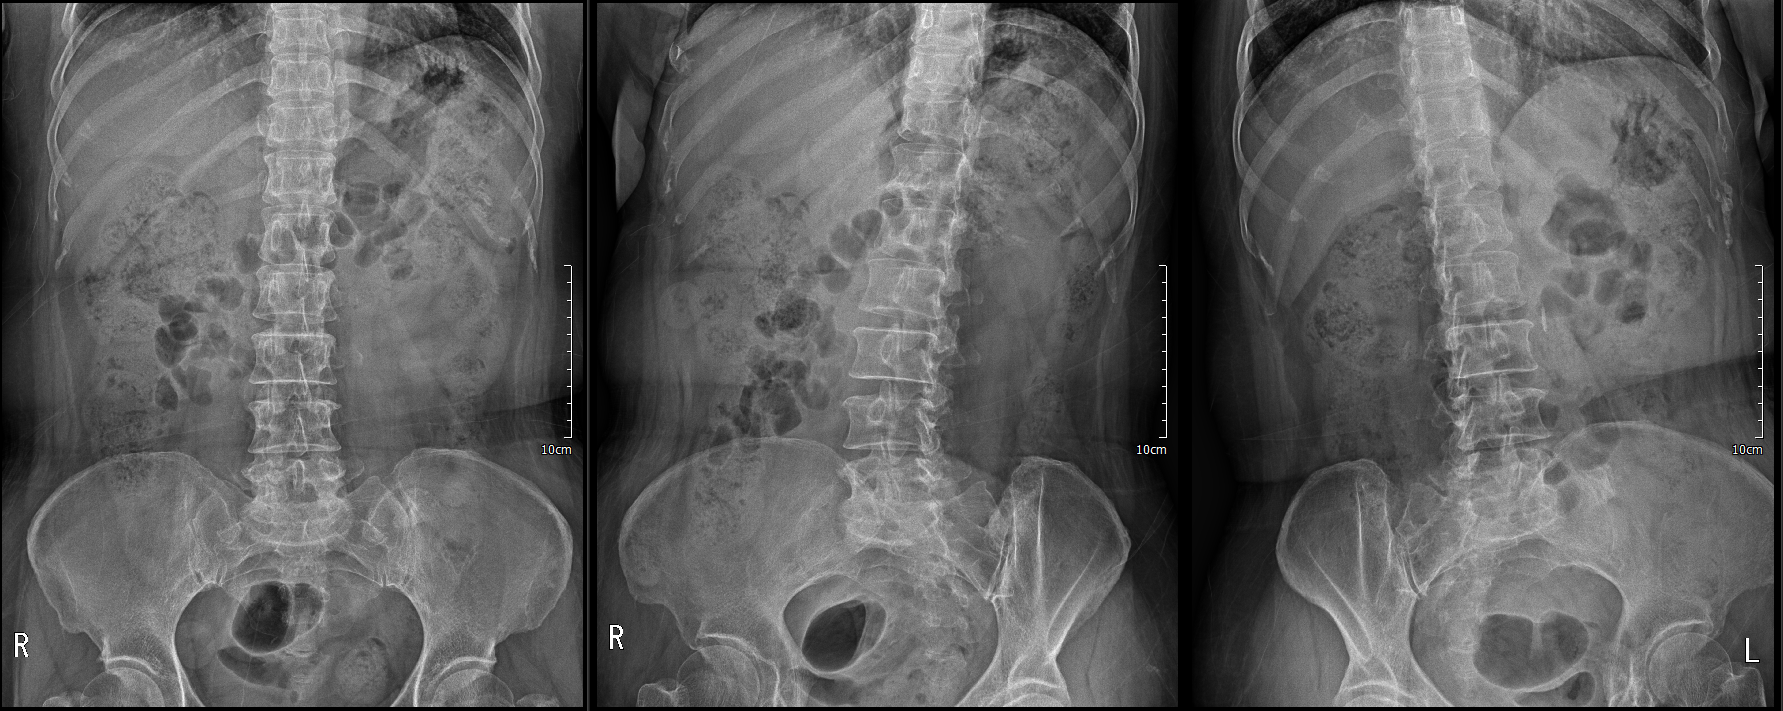

preop x ray

x ray상에서

disc space narrowing L5/S1

spondylolisthesis L5/S1 (Grade I)

lumbar degenerative change

L5 lysis